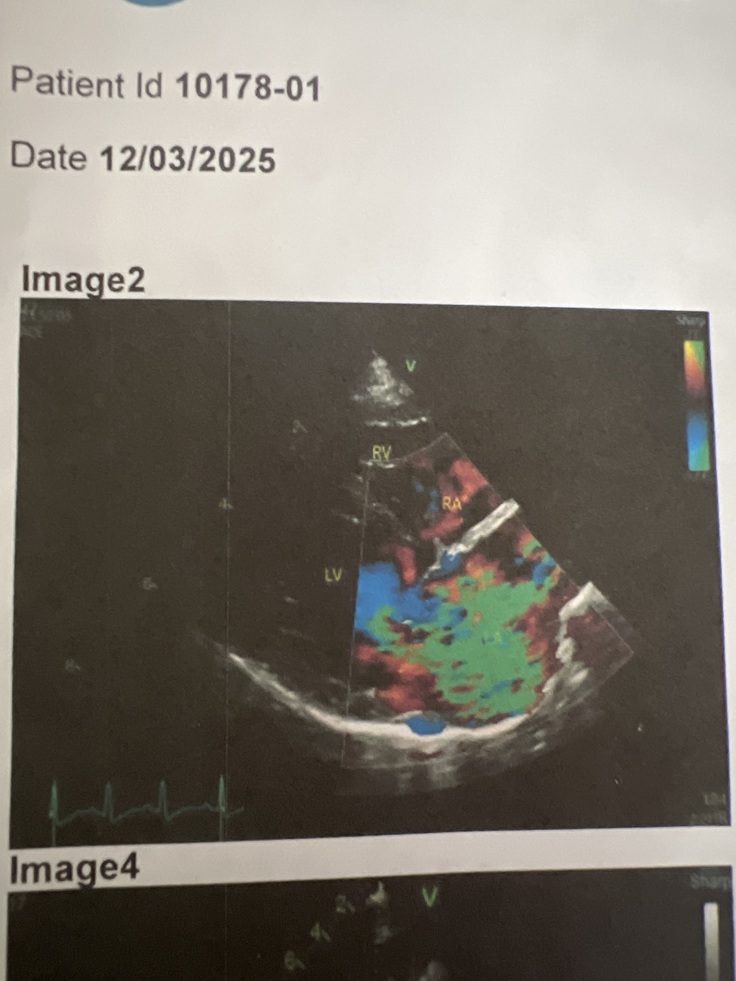

下記の画像は心臓のエコー検査(超音波検査)で、僧帽弁閉鎖不全症(心臓の弁がしっかり閉じない病気)の特徴を示しています。

Image2(カラードプラ法)

• 色(赤、青、緑)は心臓内の血液の流れを表しています。

• 左心室(LV)から左心房(LA)へ血液が逆流している様子が、緑色を含むモザイク状のパターンとして確認できます。

• 緑色は血液が乱れている(乱流)ことを示し、逆流が強いことを意味します。